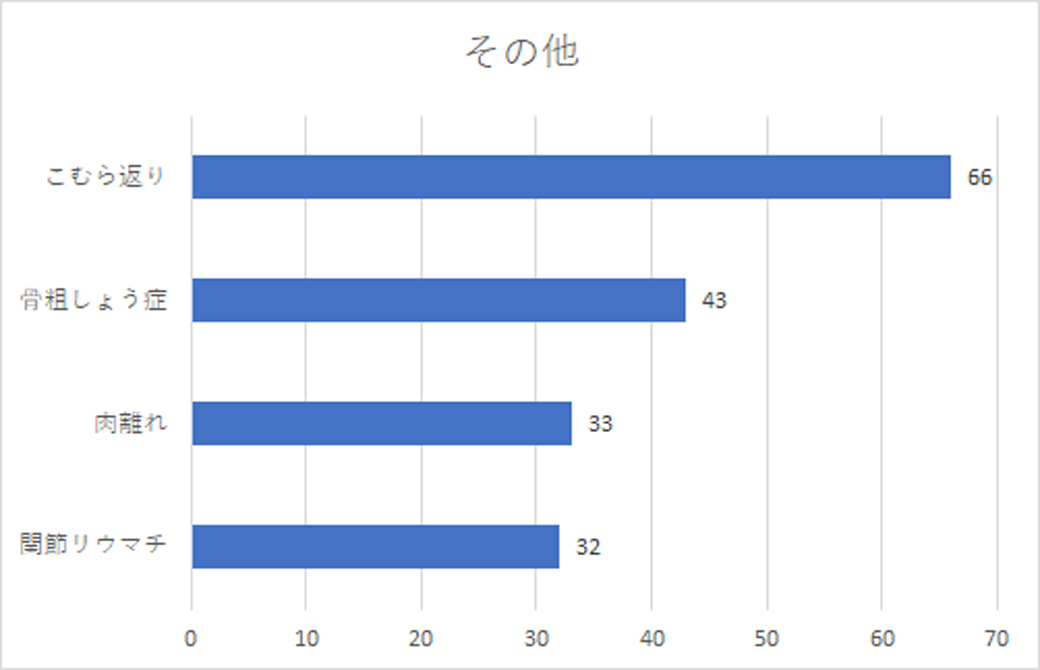

その他:足の筋肉がつる。こむら返り

その他にも、こむら返りは全体の半数近くが回答してくれました。(総回答数125名に対し、66名)。これは、ヨガクラスで特に高齢の方を教えているとよく起こる現象の1つだからでしょう。こむら返りの「こむら」はふくらはぎのこと。運動中だけでなく、夜中にふくらはぎがつるという経験をしたことがある方も多いのではないでしょうか。

筋肉の異常な収縮が原因で、痙攣を起こすこむら返り。ミネラルバランスの乱れ、脱水や冷えも大敵だと云われています。

この症状自体は、重篤ではありませんが、こむら返りを起こしやすい病気というのもあるので、裏に重大な病気が隠れていないか、あまりに頻繁に起こる場合は医療機関を受診がお薦めです。